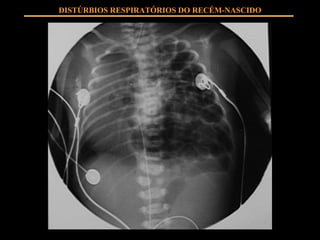

HIPERTENSÃO ARTERIAL PULMONAR Tratamento – ( não farmacológico) : Repouso Ambiente humanizado Minimização de estímulo visual, tátil e sonoro Aspiração de CET somente quando necessário DISTÚRBIOS RESPIRATÓRIOS DO RECÉM-NASCIDO

HIPERTENSÃO ARTERIAL PULMONAR Tratamento – ( farmacológico) : Alcalinização com uso de HCO3 Ventilação convencional – evitar hiperventilação Sedação e Analgesia Inotrópicos Vasodilatadores Óxido Nítrico DISTÚRBIOS RESPIRATÓRIOS DO RECÉM-NASCIDO